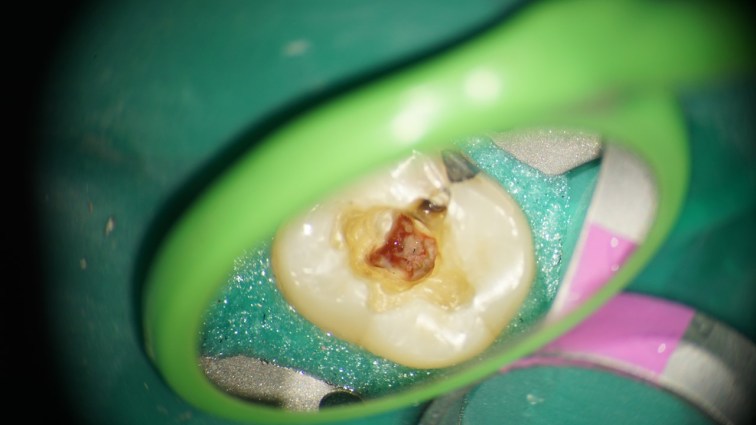

This is a “garden variety” endo. The best time to refer a case to an endodontist with a microscope is before the pulp has been touched. That way, the endodontist can control how much of tooth structure is removed to complete the endo. In this case, I had to chase all the cracks before restoring